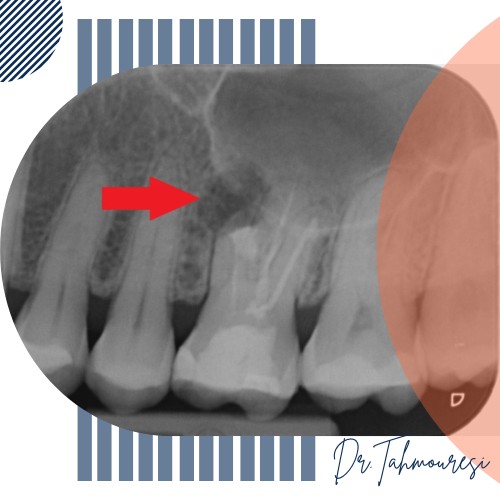

در تصاویر رادیولوژی دیجیتال دندان، عفونت معمولاً بهصورت ناحیهای تیره و با تراکم کمتر نسبت به سایر بخشها دیده میشود. این ناحیه نشاندهنده تحلیل استخوان اطراف ریشه و وجود باکتری یا التهاب است. متخصص رادیولوژی یا دندانپزشک از روی این الگوی خاص میتواند محل و شدت تقریبی عفونت را تشخیص دهد.